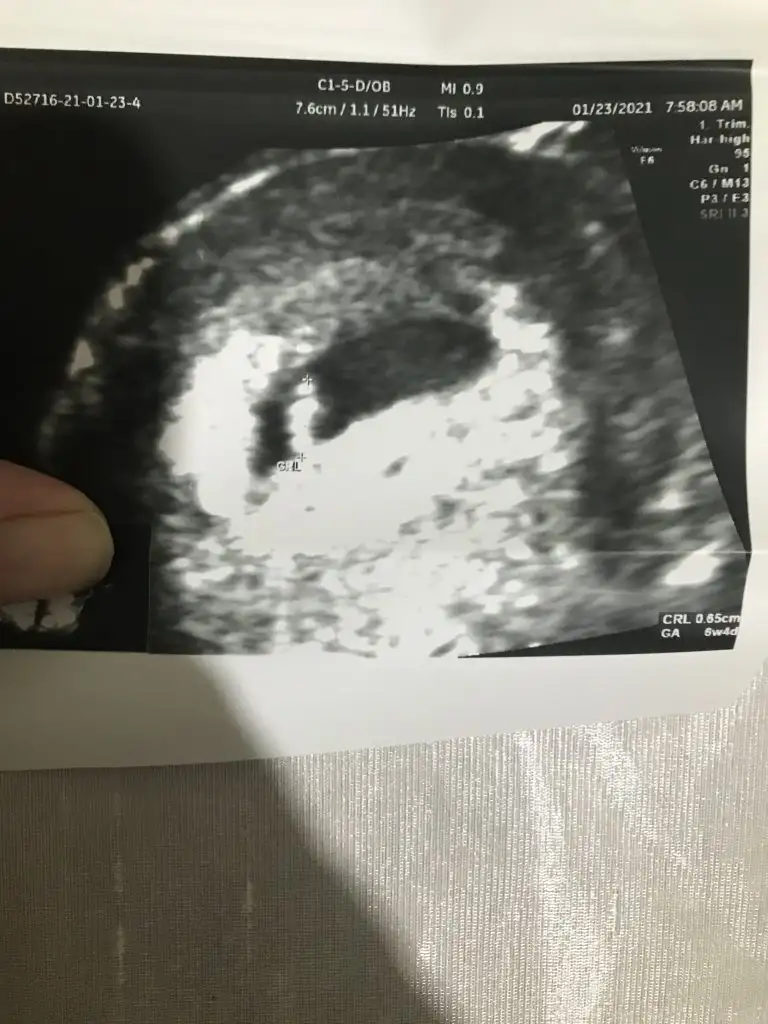

8+6 günlük cinsiyet tahmini yaparmısınız 😀😀 karından muayne resimleri

• E0495172-A4C8-4CF7-BC42-83D49B693CA3.webp

E0495172-A4C8-4CF7-BC42-83D49B693CA3.webp

46,3 KB · Görüntüleme: 196

• 58C22708-428B-4737-8308-3775BAAD2810.webp

58C22708-428B-4737-8308-3775BAAD2810.webp

52,1 KB · Görüntüleme: 163

• 6287B562-5B80-4D5D-9531-EDF1542C9421.webp

6287B562-5B80-4D5D-9531-EDF1542C9421.webp

25,8 KB · Görüntüleme: 154

• 54FFD939-75F9-47CA-B40E-B302C566F091.webp

54FFD939-75F9-47CA-B40E-B302C566F091.webp

46,6 KB · Görüntüleme: 238